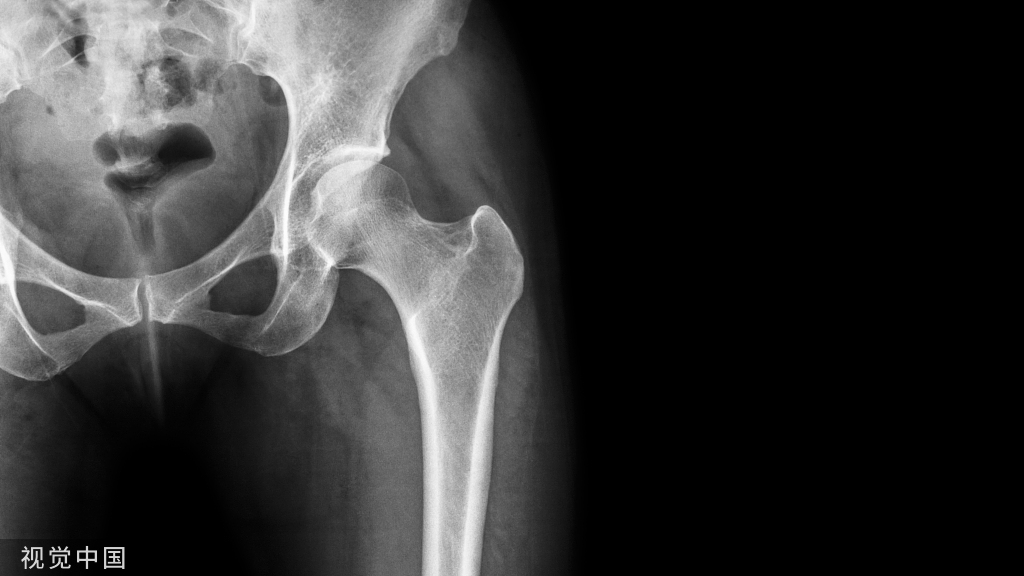

我们可以拿一张典型骨盆X线片为基础,对髋骨、盆骨和髋关节特点进行解读……

△ 图1 骨盆正位片

常规投照正位(如图所示)

骨盆的X线解剖

骨盆一般投照前后位,检查骶、尾骨时可加照侧位,检查骶髂关节时应加照45°斜位,产科骨盆测量另有其特殊投照方法。

骨盆前后位片上,骶骨中线应通过耻骨联合。骶髂关节左右对称,关节间隙下半部分可以显示,上半部常投影出模糊双线影。界线的影像在女性呈卵圆形,在男性略呈鸡心形。髂嵴连线影正好通过第4、5腰椎间隙。

由髂嵴影向外可追踪到骼前上、下棘,由髂前下棘到股骨颈外上缘的连线称髂颈线,用以判定髋关节是否正常。正位片上,可以测量耻骨下角,男性为锐角,女性为钝角。

女性骨盆径线的测量,可以采用正位(见图1)和侧位。正位片上,界线影像最远点连线为入口横径,正常为12.3 cm;两侧坐骨棘连线为中骨盆横径,正常为10.5 cm;两侧坐骨结节间距为小骨盆出口横径,正常为11.8 cm。

侧位片上,耻骨联合后缘上端到骶骨岬连线为小骨盆入口前后径,正常为11.6 cm;耻骨联合后缘下端和坐骨棘中点的连线延长到骶骨的前缘,为中骨盆前后径,正常12.2 cm;耻骨联合后下缘到骶尾关节的连线,为小骨盆出口前后径,正常11.8 cm。

髋关节的X线解剖

常规拍摄正位(见图1)和侧位X线片。